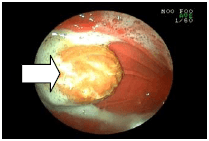

![]() |

吐き気が続いている犬の胃の中を調べてみました。 大きなポリープが出来ていました。(矢印) |